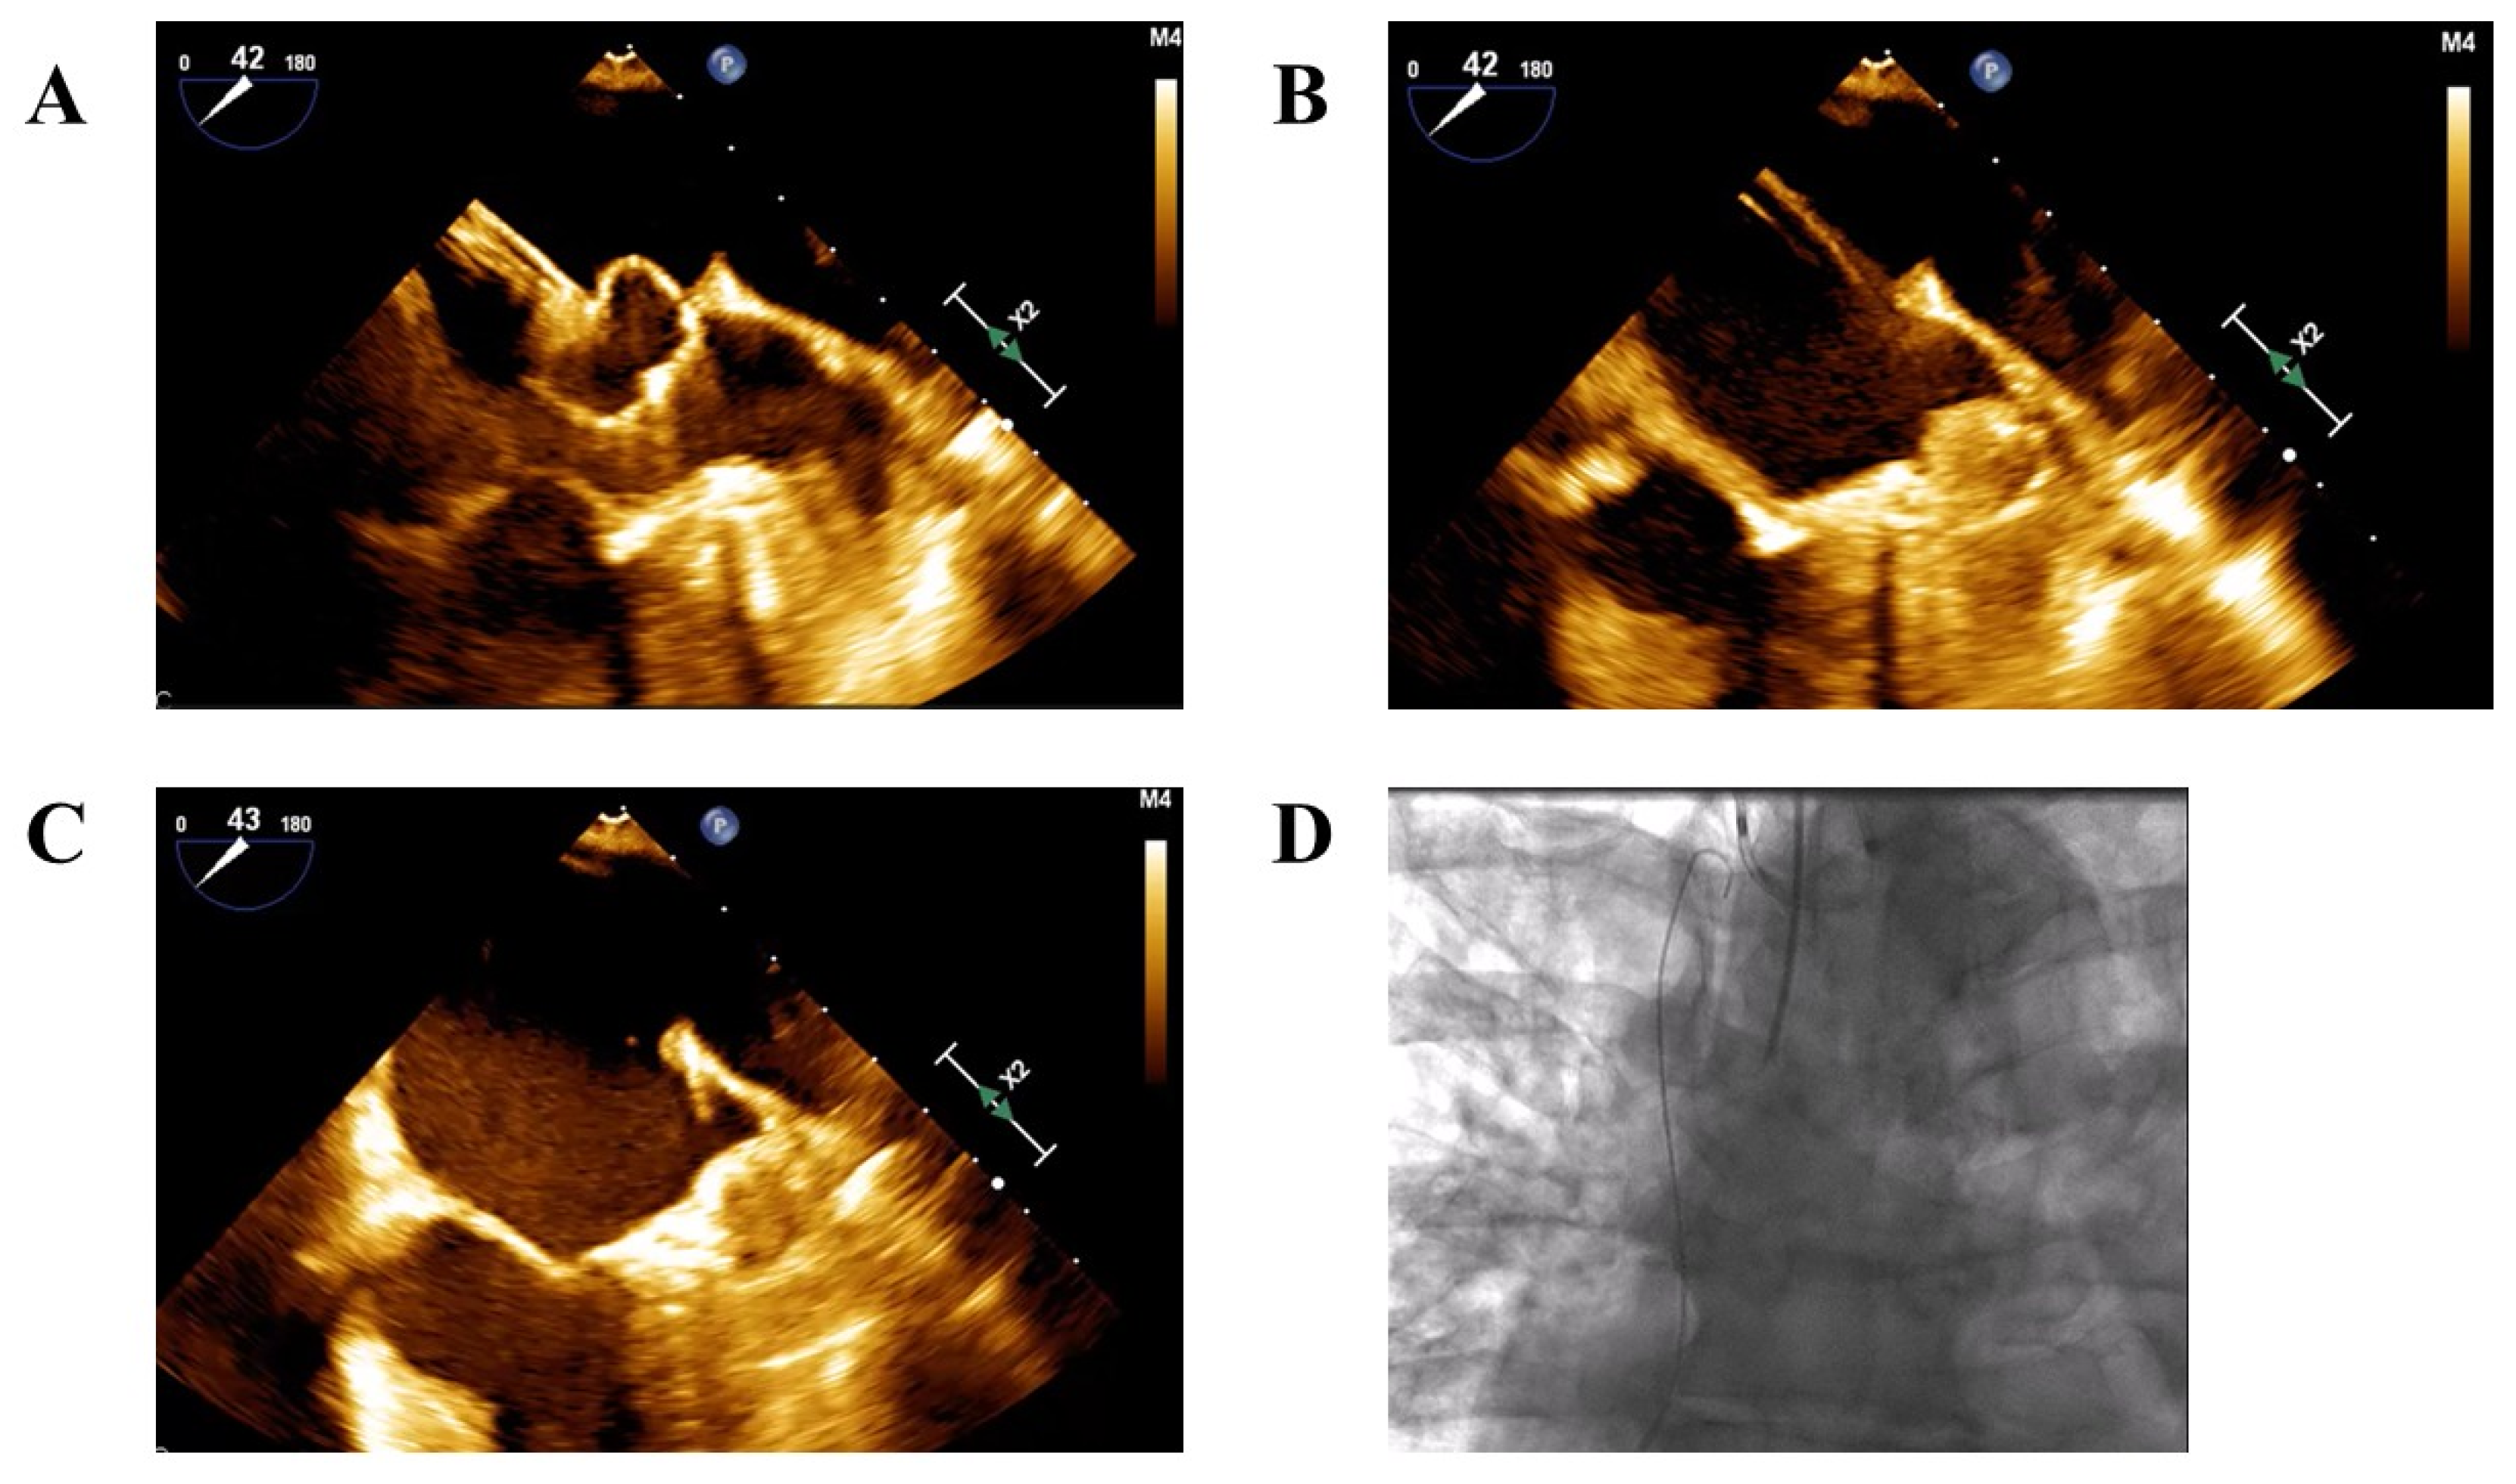

- Cautious advancement of the device and sheath into the LAA only after partial deployment of the device—either the lobe in Amplatzer devices or the ball-shaped structure in Watchman devices to reach the intended landing zone (Figure 1A–C).